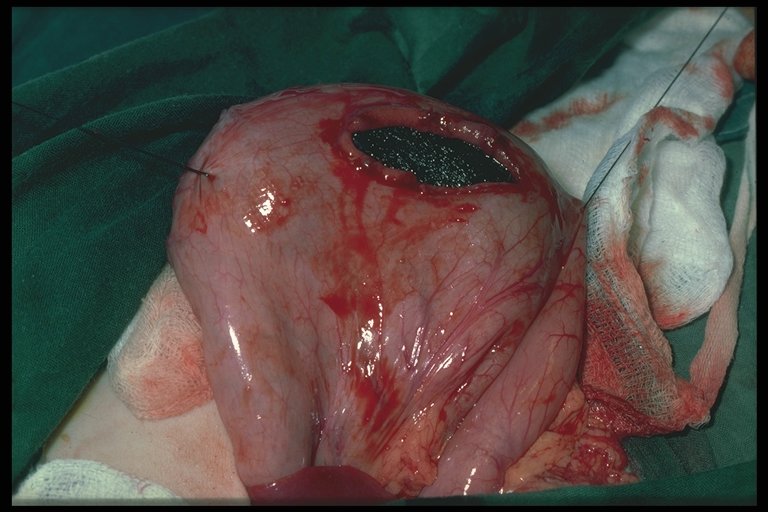

A Meckel's diverticulum is found adherent to the anterior abdominal wall at umbilicus. The attached band (omphalomesenteric or Meckel's band) caused small bowel obstruction in this child